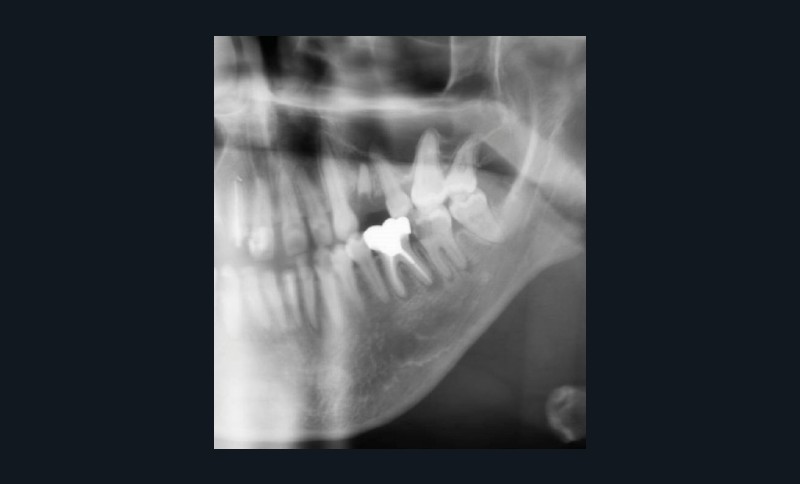

Dans le bilan avant mise en place du traitement, les recommandations, notamment de rhumatologie, indi-quent la réalisation d’un bilan dentaire et la mise en œuvre des soins nécessaires [1]. Cela a pour but d’identifier les foyers infectieux en présence et de les prendre en charge avant que le traitement ne débute, donc avant que le patient présente un risque infectieux accru (fig. 2).

Pour les actes invasifs, une suspension de traitement pourra être discutée avec le médecin prescripteur, afin de réduire le risque infectieux au moment de l’acte, mais aussi en postopératoire [1, 2]. La thérapeutique sera reprise lorsque la cicatrisation sera complète. Il est évident que cette suspension de traitement ne doit pas altérer le pronostic de la pathologie et l’état général du patient. En cas d’urgence, les actes nécessaires doivent être entrepris sans délai (fig. 3).